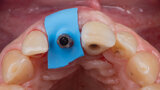

Immediate placement and restoration of a Straumann BLX implant replacing maxillary incisors